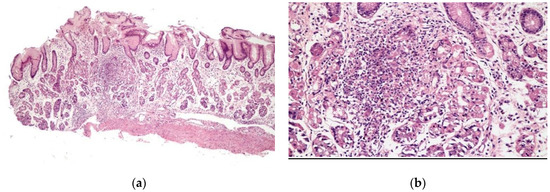

Chronic gastritis was identified in the body in 52 patients (89.7%) and in the antrum in 51 patients (87.9%), with a predominance of mononuclear cells in 37 patients (63.8%) and discrete infiltrate of the lamina propria in 35 patients (60.3%). Histopathological alterations were present in 18 of 19 patients (94.7%) of the patients with erosive gastritis, and in 13 of 13 patients (100%) with erythematous gastritis. Focally enhanced gastritis (FEG) was identified in four patients (6.9%), all of whom were H. pylori-negative (Figure 2), two with erythematous gastritis and two with erosive gastritis. Epithelioid granuloma was not found.

Figure 2.

Focal enhanced gastritis: mononuclear inflammatory infiltrate associated with focal destruction of glands. Lesion intensity contrasts with slight inflammatory infiltrate in the remaining lamina propria. (a) H&E × 40; and (b) H&E × 100.